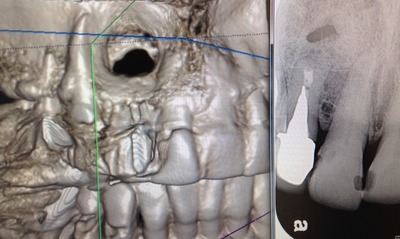

レントゲンで根の先が黒くなり、

膿んで骨がとけて、

ここに穴が開いてますね!

細菌が根の先にまで 進入してくると、

骨の細胞は細菌と戦えないんです。

一旦、骨がとけて肉芽って呼ぶ炎症性のお肉に変わります。

こんなに大きな穴でも、治ります。

少し根っ子を削るので、短くはなりますが。